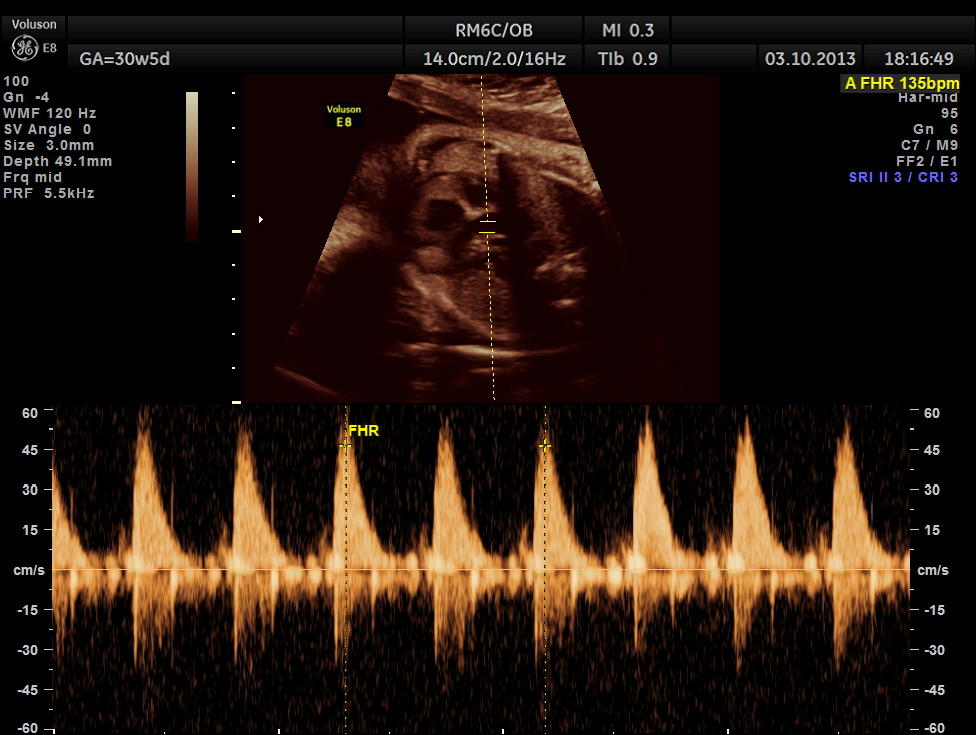

The following pictures belong to two scans done at 31 weeks of gestation.

The umbilical artery doppler appeared to be normal. MCA was technically difficult to access.